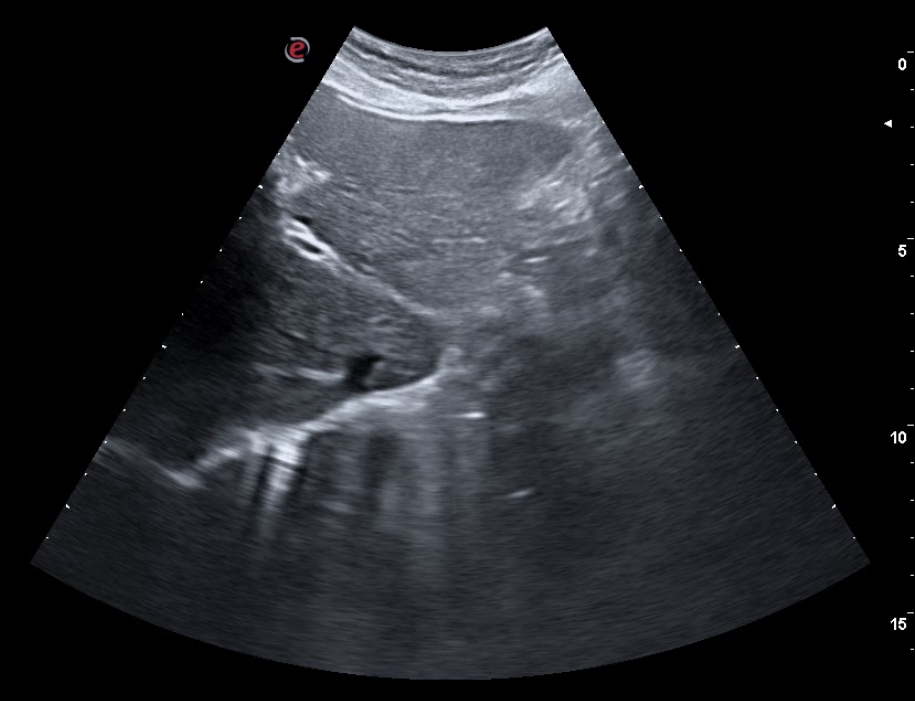

En consulta decidimos realizar ecografía clínica abdominal mostrando hígado de ecoestructura y tamaño adecuados, con vena porta y suprahepáticas permeables, con vesícula biliar repleccionada sin ecos en su interior, páncreas visible sin alteraciones, riñones con buena diferenciación córtico-medular con vejiga reflexionada sin ecos en su interior, útero involucionado, y una masa dependiente de fosa ilíaca derecha de 5×5 cm de ecoestructura similar a un riñón, correspondiente al área explorada.